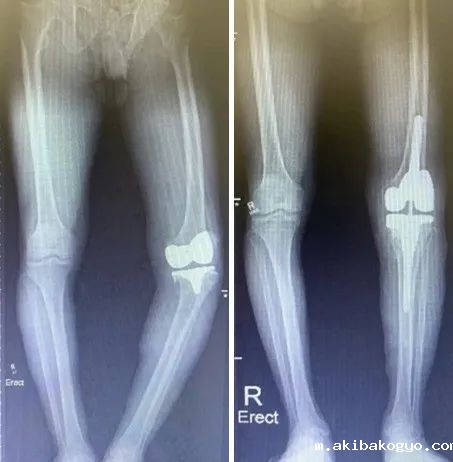

关节外科是深圳市最早开展关节置换手术早期加速康复(ERAS)的团队,在国际知名关节置换专家曲广运教授的带领下,以亚洲最具影响力的人工关节医疗和培训中心—香港大学玛丽医院关节外科为依托,已开展包括髋、膝、肩等关节在内的多项关节外科手术。

团队对于人工假体周围感染、假体松动等问题的诊断和治疗经验具有丰富经验,成功开展包括间置器植入术、人工关节翻修术等高难度手术。

特色优势项目:关节置换围手术期的快速康复;膝关节骨性关节炎的综合性非手术治疗方案的推广、机器人辅助下关节置换手术的开展、围手术期可穿戴装备行定量功能锻炼及居家康复。